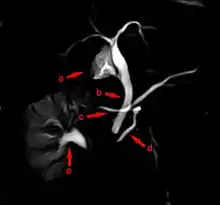

The most common and accurate way of diagnosing an individual with this anomaly is by MRCP (Magnetic Resonance Cholangiopancreatography) or ERCP (Endoscopic Retrograde Cholangiopancreatography). This test can demonstrate the presence of two separately draining ducts within the pancreas. Other tests can assist doctors with diagnosis, such as a CT scan and an MRI.